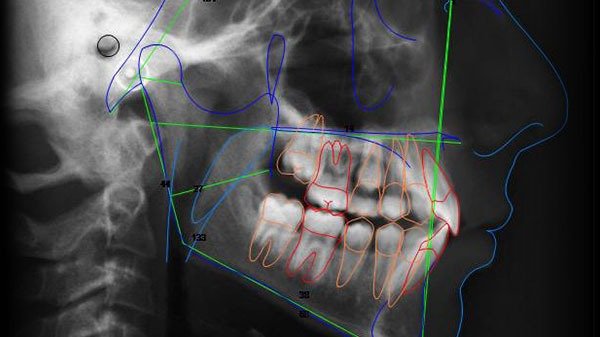

La Telerradiografía es una técnica radiográfica que captura imágenes laterales o frontales del cráneo, utilizada principalmente en ortodoncia y ortopedia maxilofacial. Este procedimiento permite a los especialistas realizar estudios cefalométricos para evaluar la relación entre los maxilares, los dientes y las estructuras craneales.

La telerradiografía lateral muestra una vista de perfil del cráneo, ideal para análisis cefalométricos. Permite evaluar:

• Relación entre maxilar y mandíbula

• Ángulos craneofaciales (ANB, SNA, SNB)

• Inclinación de los incisivos